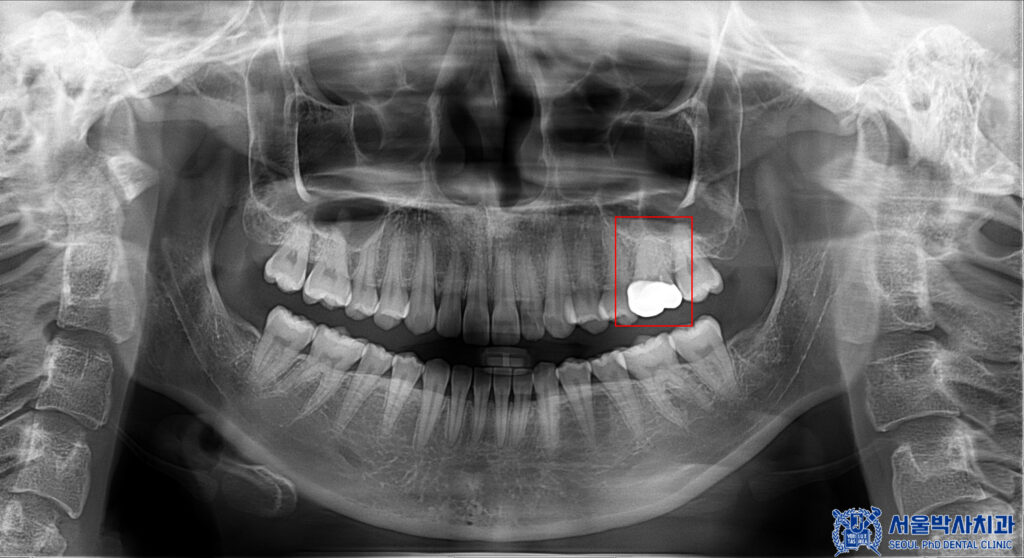

파노라마를 촬영하여 확인해 보니,

뿌리 쪽에 염증이 있는 것을

볼 수 있었는데요.

겉으로 보이는 크라운에는

특별한 문제가 없어 보였지만,

방사선 사진상 치아 뿌리 끝 주변으로

뼈가 손상된 소견이 확인되었습니다.

이는 치아 내부 신경에 염증이 생기면서

뿌리 끝까지 번진 상태로,

추가적인 치료가 필요한 상황이었습니다.